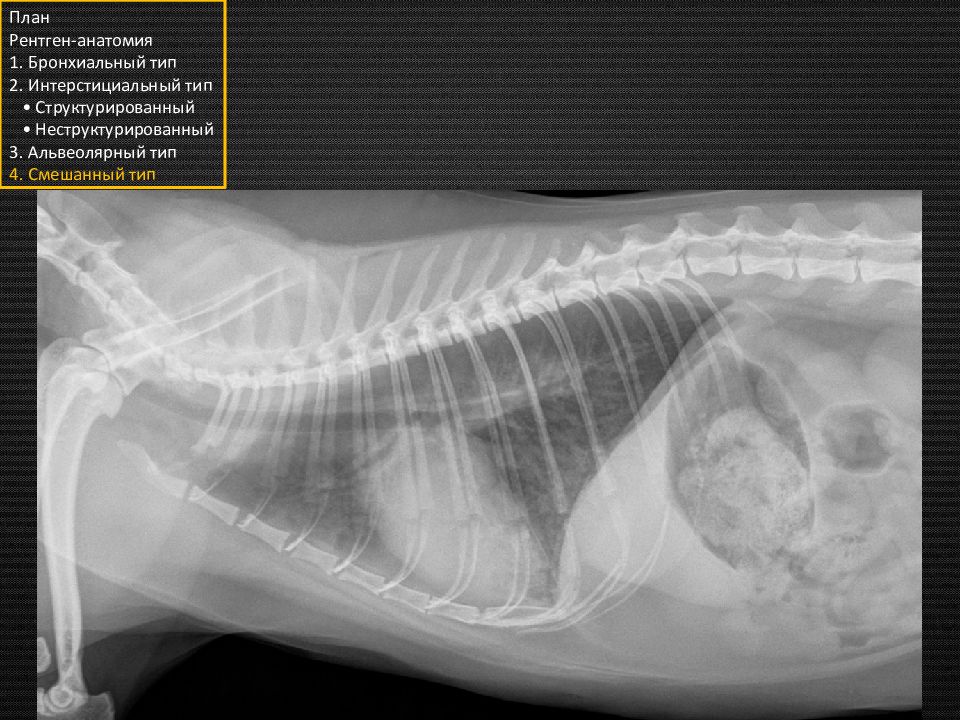

Собака. Грудная клетка нормальной формы План Рентген-анатомия 1. Бронхиальный тип 2. Интерстициальный тип • Структурированный • Неструктурированный 3. Альвеолярный тип 4. Смешанный тип